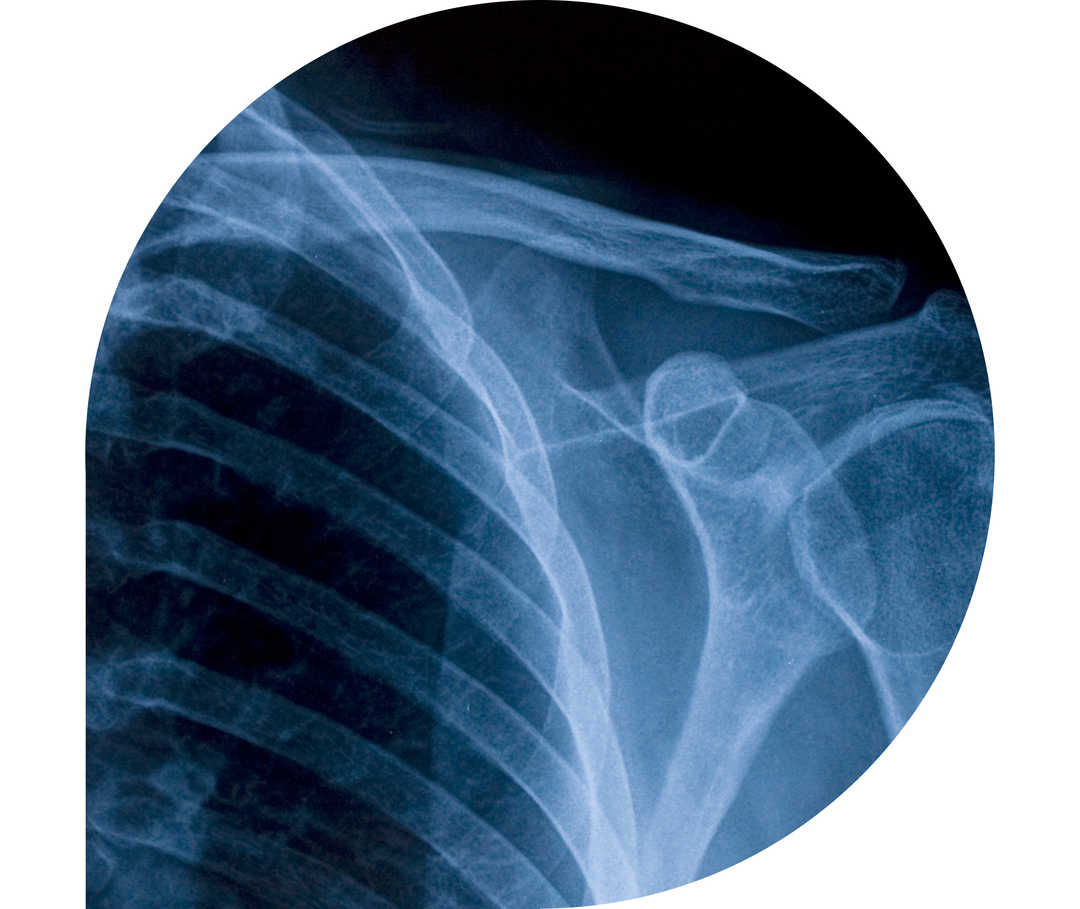

Die Polymyalgia rheumatica (PMR) ist eine entzündlich-rheumatische Erkrankung. Direkt übersetzt bedeutet sie „Vielmuskelschmerz“. Die dabei auftretenden Entzündungen der Schulter-, Rücken- und Nackenmuskulatur führen zu Schmerzen und Steifheit in den jeweiligen Regionen. Auch die Hüftmuskulatur kann betroffen sein. Die Polymyalgia rheumatica ist der Riesenzellarteriitis sehr ähnlich, häufig treten beide Erkrankungen sogar zusammen auf. Forscher*innen sind sich nicht einig, ob es sich überhaupt um zwei unterschiedliche Krankheiten handelt oder Polymyalgia rheumatica und Riesenzellarteriitis nicht Folgen desselben Krankheitsprozesses sind. Aus diesem Grund wird die Polymyalgia rheumatica häufig auch zu den Vaskulitiden (durch eine Fehlsteuerung des Immunsystems ausgelöste Gefäßentzündungen) gezählt.1,2,3,4,5